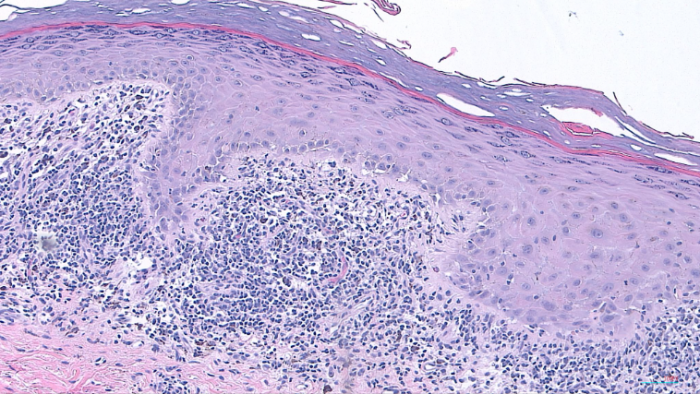

DERMATOHISTOPATHOLOGY:

The histopathological examination revealed several notable features consistent with a lichenoid tissue reaction. There was a band-like lichenoid infiltrate present in the papillary dermis, along with interface vacuolar degeneration affecting the basal cell layer of the epidermis. Additionally, pigmentary incontinence was observed in the upper dermis, indicative of melanin leakage. Hypergranulosis was noted, characterized by an increase in granules within the keratinocytes. The rete ridges exhibited a saw-tooth appearance, and Civatte bodies, which are apoptotic keratinocytes, were also identified.